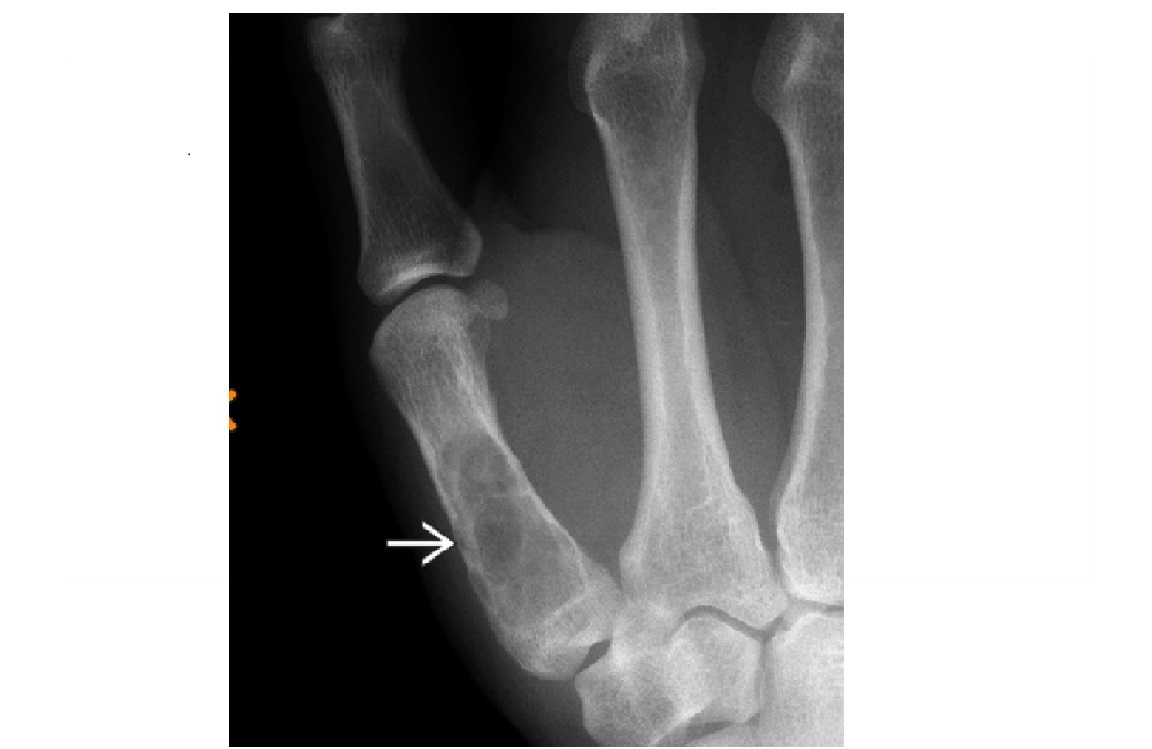

ENCHONDROMA

Commonest location Hands/feet

Long bones: proximal humerus > distal and proximal femur > proximal tibia

Intramedullary and metaphysis

multiple enchondroma

Maffuci - haemangioma

Olliers - multiple enchondroma only

DDx

-Brown tumor (hyperparathyroidism),

-sarcoid - lace like bone lesion phalanges

-intraosseous ganglion

-metastatic disease.

MRI

T1: low to intermediate signal

Fluid-sensitive sequences: lobulated high signal typical of cartilage lesions

Enhancement: peripheral and septal, accentuating lobules